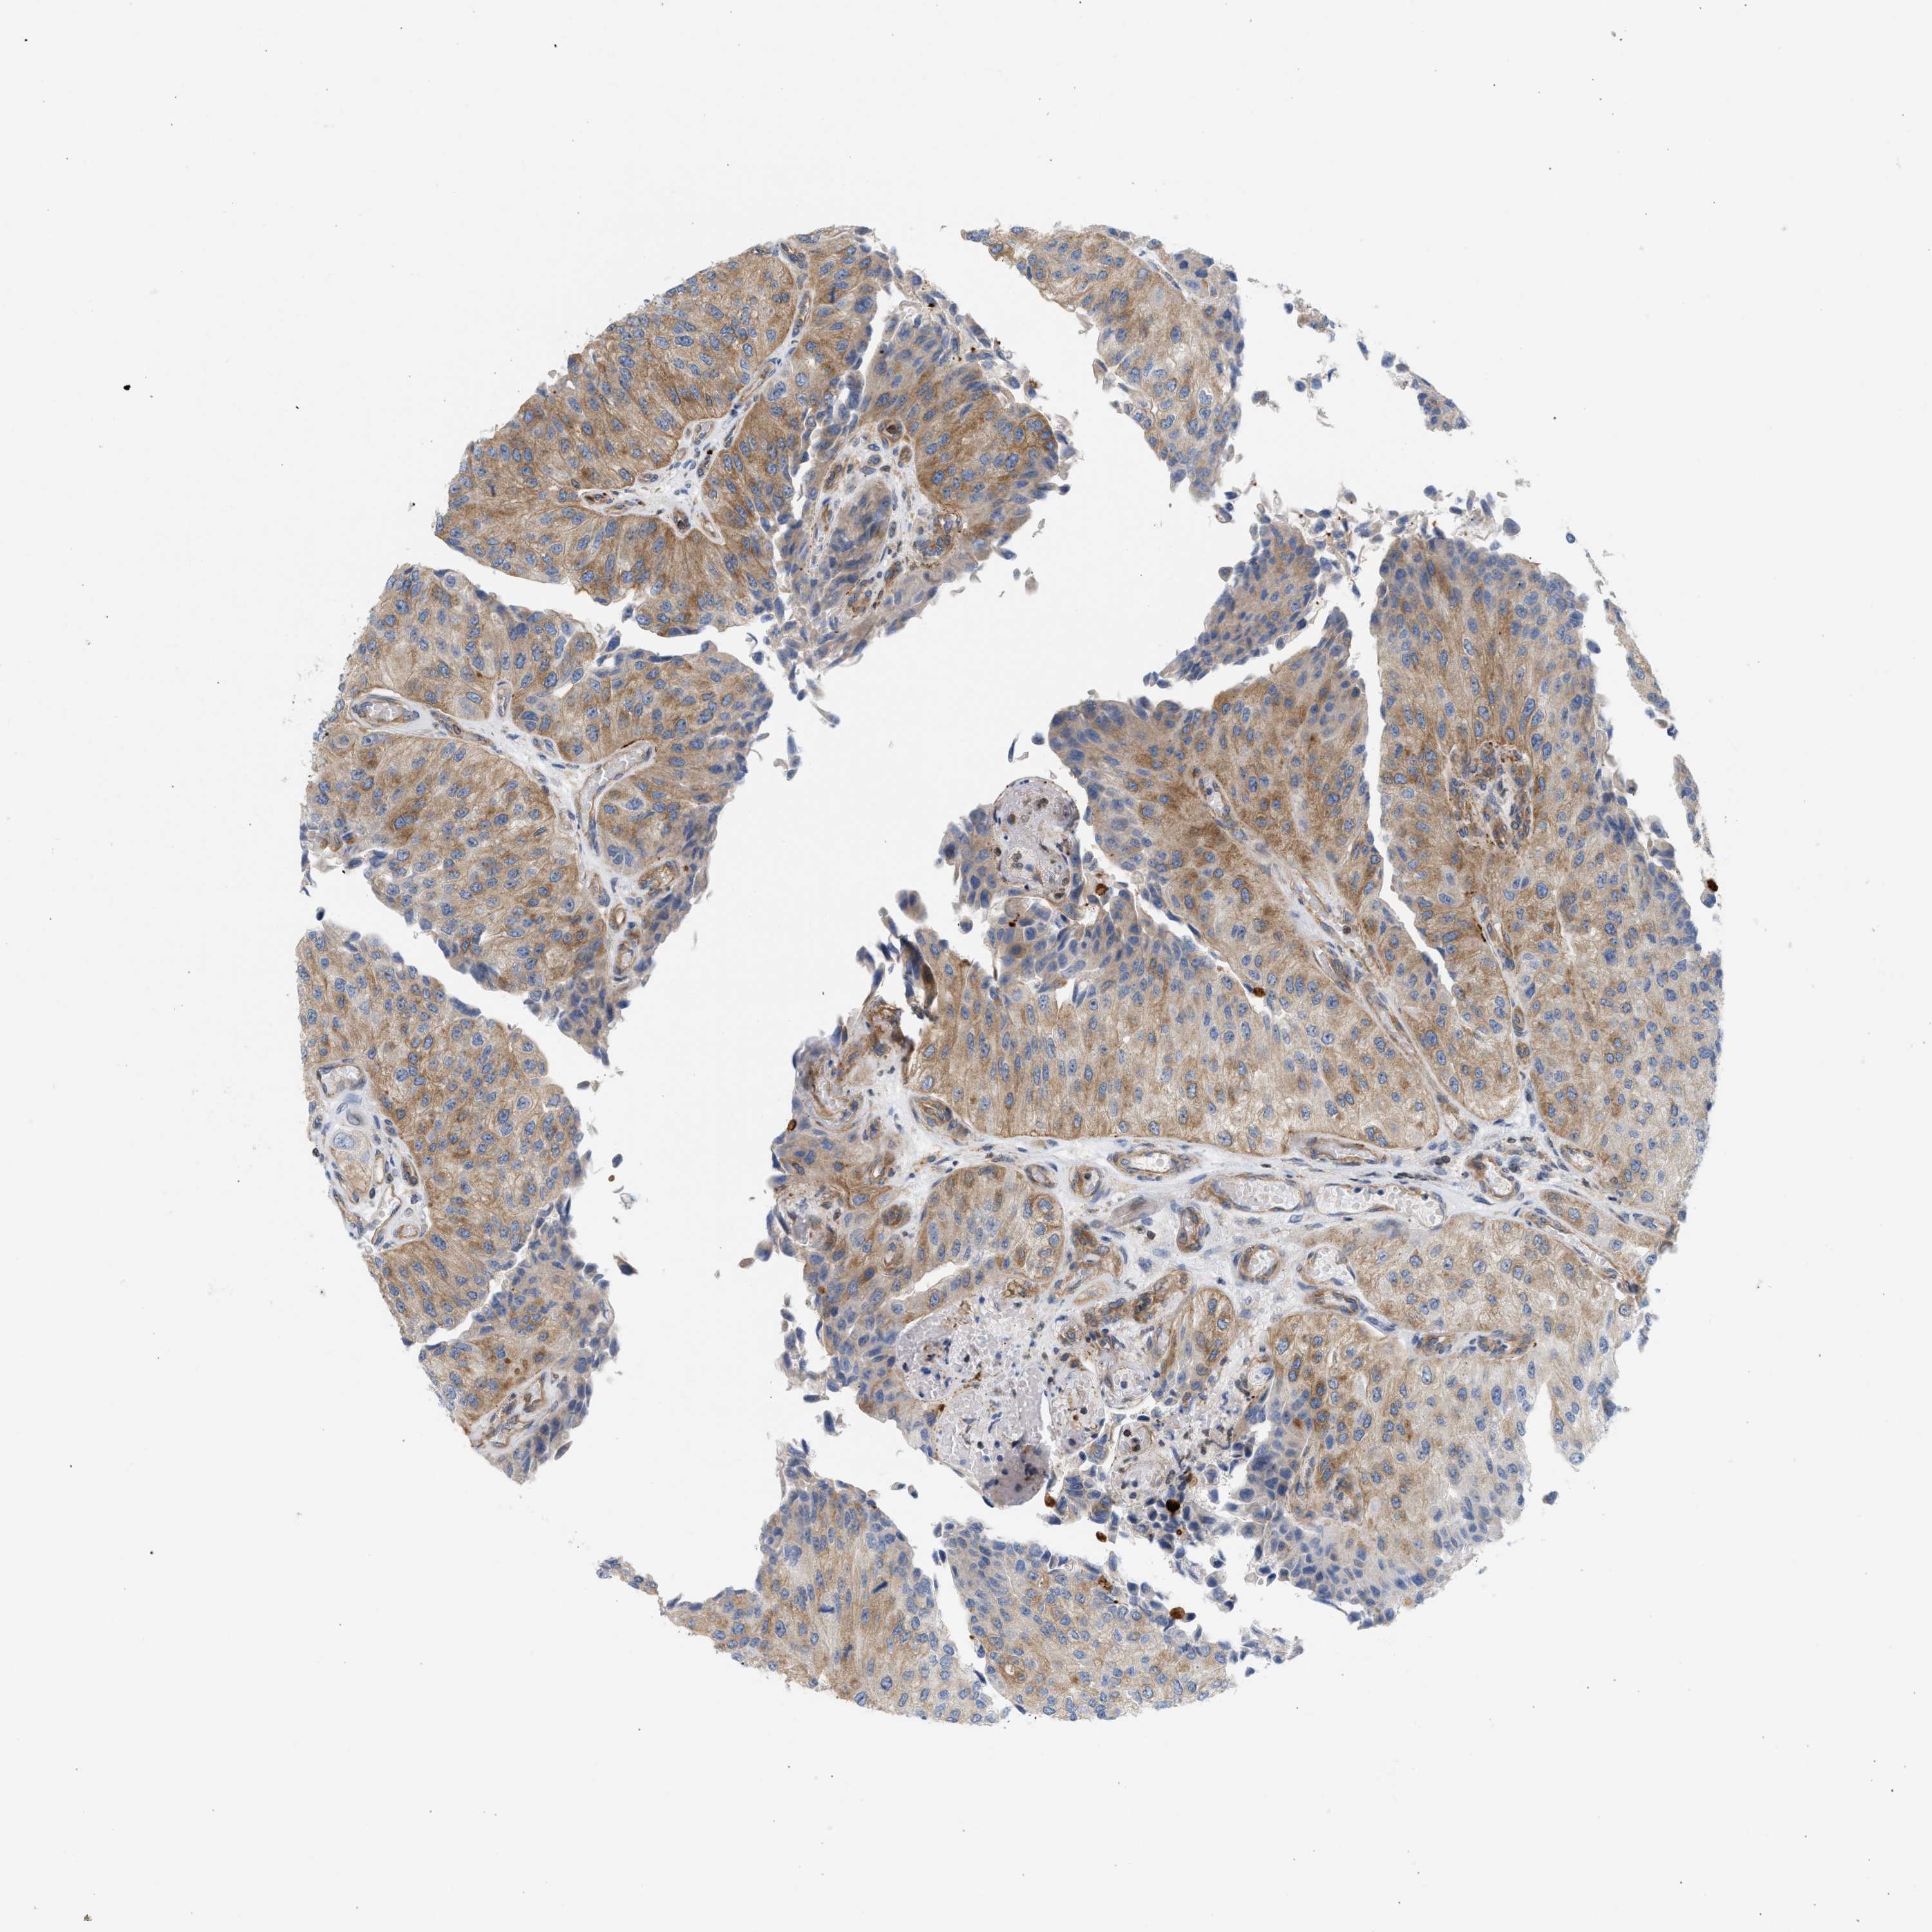

UROTHELIAL CANCER - Protein expressioni

A mouse-over function shows sample information and annotation data. Click on an image to view it in a full screen mode. Samples can be filtered based on level of antibody staining by selecting one or several of the following categories: high, medium, low and not detected. The assay and annotation is described here.

Note that samples used for immunohistochemistry by the Human Protein Atlas do not correspond to samples in the TCGA dataset.

Antibody stainingi

Antibody staining in the annotated cell types in the current human tissue is reported as not detected, low, medium, or high, based on conventional immunohistochemistry profiling in selected tissues. This score is based on the combination of the staining intensity and fraction of stained cells.

Each image is clickable and will lead to virtual microscopy that enables deeper exploration of all samples and also displays staining intensity scores, fraction scores and subcellular localization as well as patient and tissue information for each sample.

Antibody HPA017286

Staining

High

Medium

Low

Not detected

Intensity

Strong

Moderate

Weak

Negative

Quantity

>75%

75%-25%

<25%

None

Location

Nuclear

Cytoplasmic/membranous

Cytoplasmic/membranous,nuclear

Urothelial carcinoma, Low grade

Urothelial carcinoma, High grade